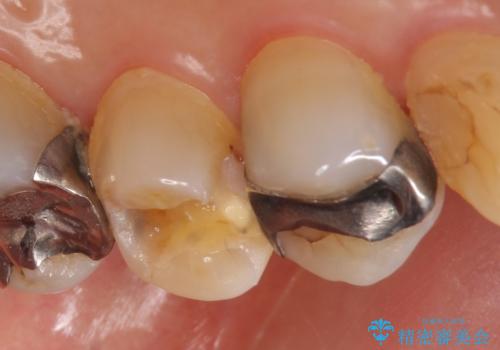

- 左上5番目の歯の銀歯が外れてしまったため、セラミックインレーによる修復を行った症例です。

手前の左上4番目の歯も虫歯だったため、セラミックインレーによる修復を行いました。